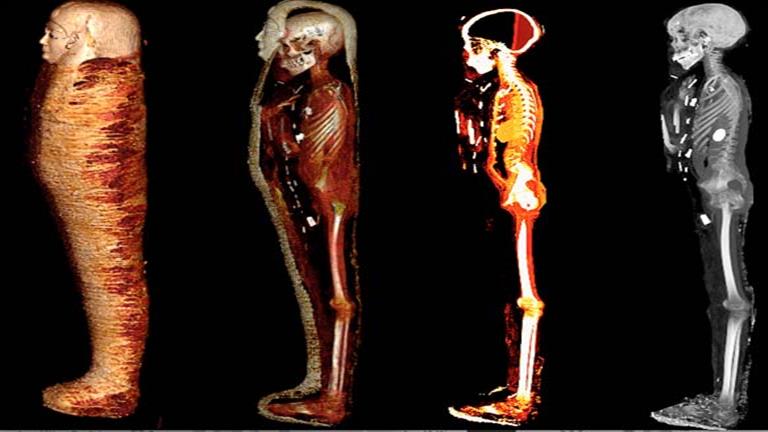

كشفت الأشعة المقطعية والطباعة ثلاثية الأبعاد أسرار مومياء الصبي الذهبي المخزنة في بدروم المتحف المصري بالتحرير لأكثر من قرن من الزمان.

تم العثور على هذه المومياء ملفوفة بالكامل بالكتان عام 1916، داخل مقبرة من العصر البطلمي (حوالي 300 ق.م.) بمدينة إدفو بمحافظة أسوان حيث تم نقلها وحفظها، آنذاك، ببدروم المتحف المصري بالتحرير دون فحص لأكثر من قرن من الزمان، حتى تم فحصها لأول مرة عام 2015 من قبل د. سحر سليم أستاذ الأشعة بكلية الطب جامعة القاهرة بالتعاون مع صباح عبد الرازق مدير عام المتحف المصري بالتحرير ومحمود الحلوجي المدير الأسبق للمتحف، باستخدام الأشعة المقطعية، بشكل آمن، من خلال الجهاز الموجود بالمتحف واستخدام الأشعة المتقدمة وبرامج الكمبيوتر الحديثة وكذلك الطباعة ثلاثية الأبعاد.

وأضافت د. سحر سليم إلى أن الأشعة أوضحت ما بداخل اللفائف حيث ترتدي المومياء قناعًا ذهبيًا وصدرية مصنوعة من الكارتوناج وصندلًا من النسيج.

كما أوضحت صور الأشعات المقطعية الثنائية والثلاثية الأبعاد عن وجود حوالي 49 تميمة مرتبة ترتيبًا منمقًا في ثلاث أعمدة بين طيات اللفائف الكتانية وبداخل تجويف المومياء. كما أظهرت الأشعة أيضا 21 شكلًا مختلفًا للتمائم مثل عين المعبود حورس والجعران وتميمة الأفق والمشيمة وعقدة إيزيس والريشتان، وغيرهم.

ومن خلال نتائج قياسات الأشعة تبين أن 30 تميمة من التمائم المكتشفة داخل المومياء صنعت من الذهب بينما باقي التمائم صنعت من الأحجار أو الفيانس، بالإضافة إلى تميمة على شكل لسان من الذهب وضعت بداخل فم المتوفي ليتمكن من التكلم في العالم الآخر، كما يوجد تميمة على شكل أصبعين أسفل الجذع لحماية فتحة التحنيط، وتميمة أخرى كبيرة من الذهب لجعران القلب موجودة بداخل تجويف صدر المومياء، والذي تم عمل مستنسخ منه باستخدام الطباعة ثلاثية الأبعاد.

وأكدت سليم أن الدراسة كشفت عن وجه المومياء لأول مرة بعد إزالة اللفائف بشكل افتراضي بتقنية الأشعة المقطعية، حيث أتاحت الدراسة فرصة فريدة لاكتشاف أسرار تحنيط المومياء دون المساس باللفائف، وكما تركها المصريين القدماء.

وساعد استخدام التكنولوجيا والتقنيات الحديثة في التصوير الطبي بالأشعة ثلاثية الأبعاد في تقديم رؤية قيمة للمومياء، مما دعم قرار إدارة المتحف المصري بالقاهرة لنقل المومياء من بدروم المتحف لعرضها داخل قاعات العرض به، حيث لقبت بـ “مومياء الصبي الذهبي”.

وتساهم عرض صور الأشعة المقطعية بجانب المومياء في عرض متحفي مميز يمنح زوار المتحف تجربة فريدة تدعم تواصلهم مع الحضارة المصرية القديمة.